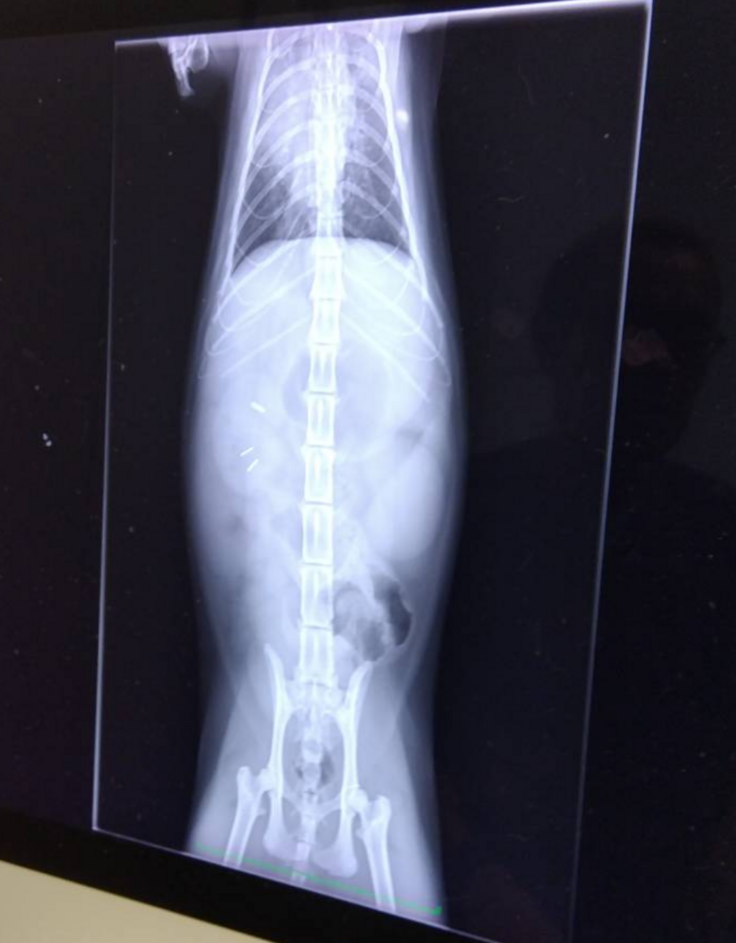

腸の病気や気になることを伝えて、触診と聴診器で診てもらってレントゲンを撮ってもらいました。

胃と大腸にガスがたまってるとのこと。

他にも気になる腸の病気や合併症の可能性、自律神経失調症や過剰摂取などもあるんじゃないかと聞いてしまいましたが、レントゲンでは分からないので、まずはこのガスを出す治療をと。

はなちゃんの場合、ずっとアンモニアが高い状態なのもあり、肝内シャントなので予後も命にかかわりますとおっしゃられました…

腸閉塞の可能性はなさそうだというのが分かっただけでも。。